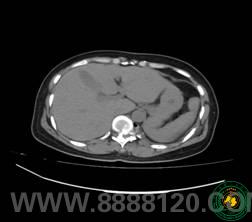

手术前CT显示椎管变形                 手术前X光片显示第十胸椎向右错位

这是一位来自筠连县城的建筑女工人,不久前在工作时不幸发生了意外,外伤后她先被送到了当地医院,当地医生经过检查后诊断为第1011胸椎脱位,受当地医疗条件所限,该患者被及时送到了我院骨科进行检查治疗。患者的CT、磁共振检查显示第1011胸椎骨折合并侧方脱位,脊髓被扭曲成S形状,并伴有多发性肋骨骨折、血气胸,这在临床上相当少见。骨科宋玉光副主任医师带领江祖洪医生等多名医务人员,待病人生命体征平稳后,为病人进行了胸椎减压复位固定融合手术。由于病人与常见的脊柱前后脱位不同,且患者没有脊髓损伤,手术难度较大,不仅要在脊椎后路操作,还要同时打开脊椎前路施行手术,而且稍有不慎就会损伤脊髓,导致病人双下肢完全瘫痪。宋玉光副主任医师成功运用360°环形减压和当今最为先进的一个切口行后路固定,侧前路减压融合手术。经过3个多小时的紧张手术,手术顺利完成,术后患者双下肢运动感觉正常如前,手术取得圆满成功。该手术的成功完成再次体现了我院骨科在宜宾市的技术领导地位。